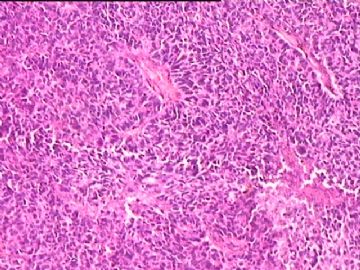

女,34y,头痛一月,右额叶占位:5*5*4cm。囊性区域,4cm。大体:3.5x3x1cm灰白间暗褐色组织一堆,质嫩。临床诊断1:胶质瘤,2:血管母细胞瘤。

• 额叶占位,胶母典型不?图3

图3

胶母

同意胶质母细胞瘤。细胞异型、坏死、核分裂、血管内皮肿胀增生均可见到。

This is certainly a WHO grade IV malignant neoplasm. While most likely a glioblastoma, I would carefully rule out PNET by staining for GFAP and neuronal markers such as synaptophysin, NeuN and NSE. Rarely, PNET may shows marked pleomorphism and indistinguishable from glioblastoma on HE stain.

同意马老师的意见,该肿瘤从形态及年龄来看考虑PNET或GBM,须标记Syn、NSE、S-100、NeuN和GFAP来鉴别。

结合图片细胞形态特点考虑胶质母细胞瘤,组化标记排除其他